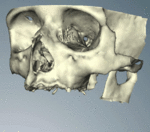

CT scans can be loaded to CAD/CAM software to create a simulation of the desired treatment. Virtual implants are then placed and a stent created on a 3D printer from the data.